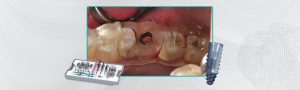

Fig. 2 – Aspecto após a remoção da coroa clínica fraturada.